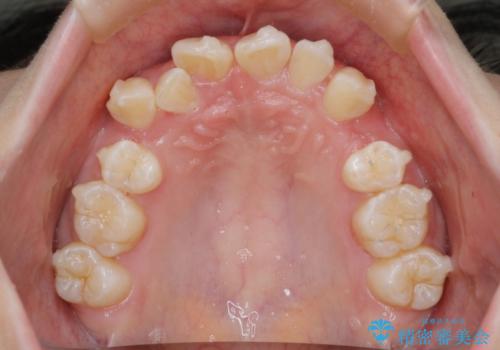

- 前歯のガタガタを主訴に来院されました。

抜歯を行い、インビザラインにて治療を完了しております。